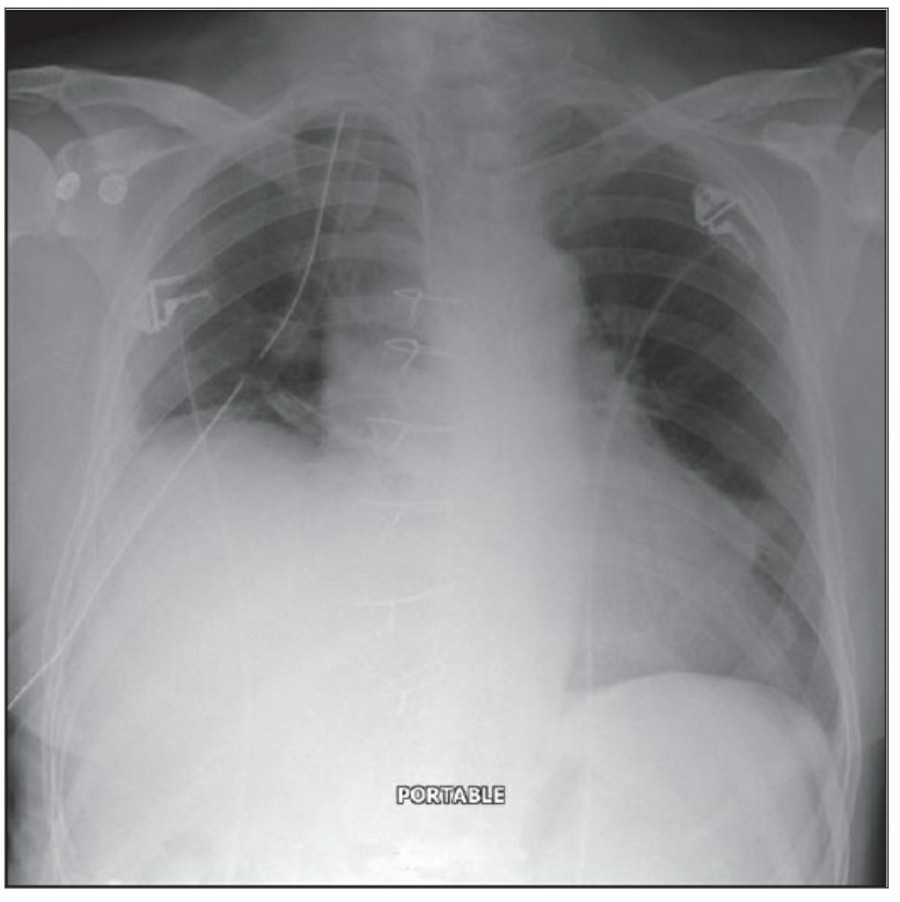

Thoracotomy를 시행받고 나온 환자의 initial postoperative chest X ray에서 각종 line과 endotracheal tube, thoracotomy tube, mediastinal drains, central venous catheter 등을 확인할 수 있을 것이다. 이러한 device들은 그 위치가 제대로 있는지 확인해야 한다.

CABG를 받은 환자에서 lower lobe atelectasis는 흔한데, 주로 왼쪽에 잘 나타나며 수일 내에 별다른 합병증 없이 회복된다. mediastinum도 약간 확대되어 보일 수 있는데, 만약 그 diameter가 많이 증가한다면 mediastinal hemorrhage 등을 시사할 수 있다. CABG 시행 후 약간의 좌측 pleural effusion은 있을 수 있지만 그 양이 많거나 증가한다면 respiratory compromise를 줄이기 위해 intervention이 필요할 수 있다. 따라서 이전의 사진과 비교를 해서 pleural effusion 양의 변화가 있는지 확인이 필요하겠다.

첫 poratable chest X ray 촬영은 각종 line과 device의 위치를 확인하는 데 꼭 필요하며, 위중한 중환자에서 cardiopulmonary disorder를 evaulation 하기 전에 이 device들 위치에 문제가 있지 않은지 확인해야 한다.